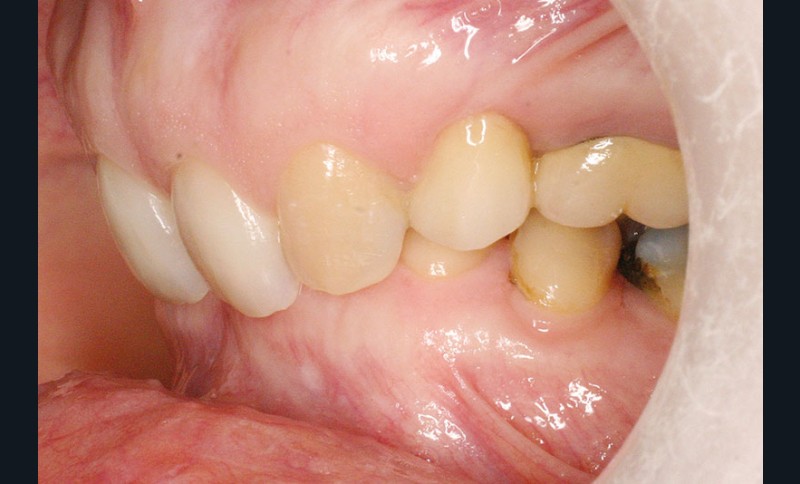

La patiente, âgée de 30 ans, présente des agénésies multiples : 12, 22, 14, 15, 24, 25, 35 et 45 (fig. 1 à 3).